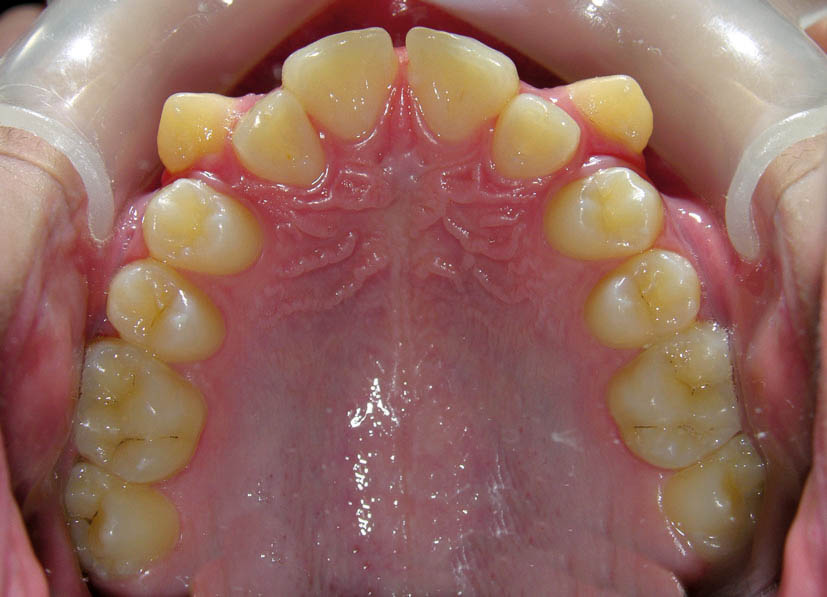

خیلی از مواقع نامرتبی نسبتاً زیادی در بالا میبینید و فکر میکنید که باید پرمولرهای بالا را کشید (شکل 96-2) اما وقتی اکلوژن را میبینید، شاهد یک اورجت صفر و یک رابطه مولری کلاسI هستید و اگر پائین غیرکشیدنی باشد، در این صورت باید دندانهای بالا را پروترود کنید تا در عین حال که مرتب میشوند یک اورجت صحیح هم به شما بدهد پس اینگونه بیماران غیر کشیدنی میشوند (شکل 96-2 الی 99-2).

شکل 96-2:کرادینگ شدید قوس بالا